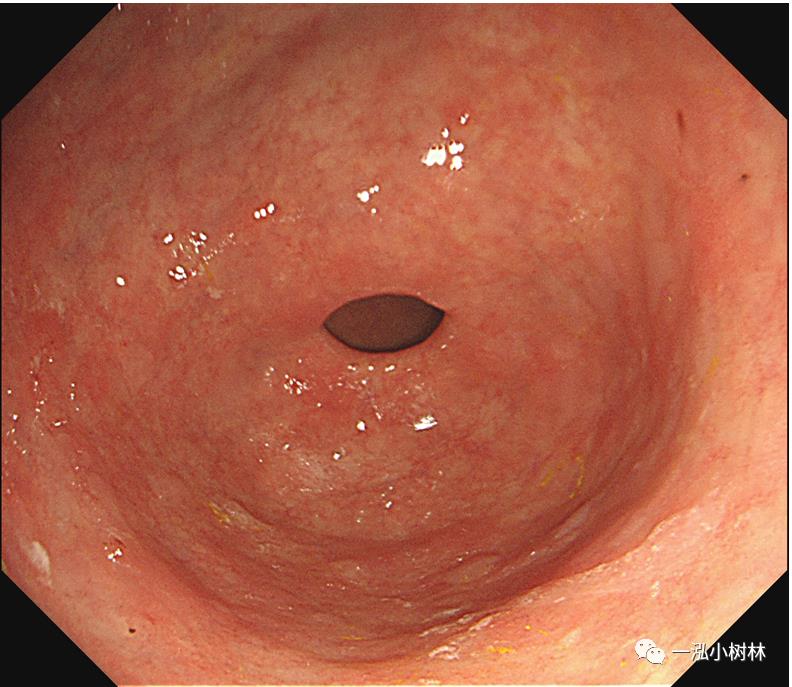

图10a 白光内镜:胃窦前壁高分化腺癌(Tub1)

图10b 白光内镜:胃窦前壁高分化腺癌(Tub1)